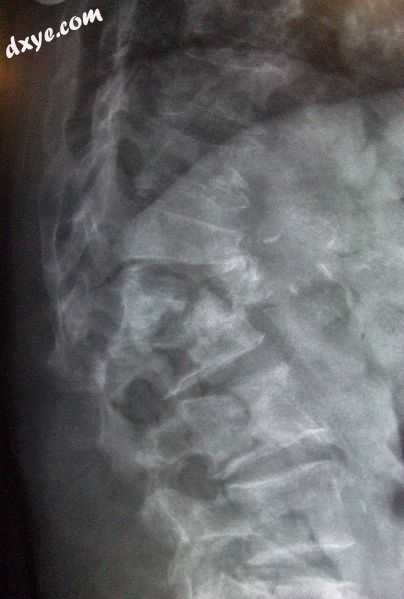

Multiple osteoporotic wedge fractures demonstrated on a lateral thoraco-lumbar s.jpg

胸腰腰椎X线片显示多发性骨质疏松性楔形骨折

常规放射照相

传统的射线照相术本身或与CT或MRI结合,可用于检测骨量减少(骨量减少;骨质疏松症)的并发症,例如骨折;用于骨量减少的鉴别诊断;或在特定临床环境中进行引导检查,例如软组织钙化,继发性甲状旁腺功能亢进或肾性骨营养不良的骨软化。然而,放射线照相术对早期疾病的检测相对不敏感,并且需要大量的骨质流失(约30%)才能在X射线图像上显现出来。

全身性骨质疏松症的主要影像学特征是皮质变薄和放射线透亮度增加。骨质疏松症的常见并发症是椎骨骨折,脊柱X线摄片可以极大地帮助诊断和追踪。可以使用平片X射线客观地进行椎骨高度测量,方法是使用多种方法,例如高度损失和面积减小,特别是在观察T4-L4的垂直变形时,或者通过确定考虑到脊椎骨折的脊柱骨折指数涉及的椎骨数量。累及多个椎体会导致胸椎的后凸,从而导致所谓的dowager峰。